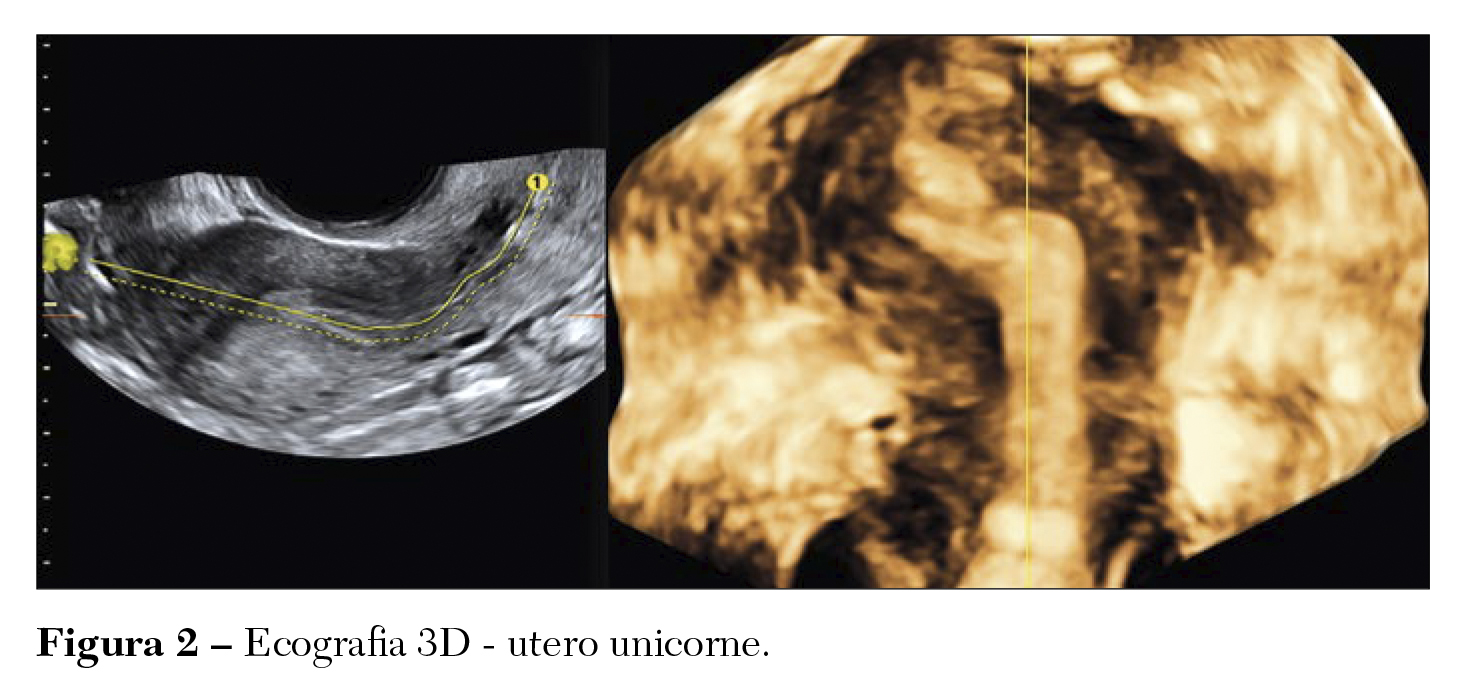

L’ecografia tridimensionale (3D) è raccomandata, invece, in caso di sospetto di anomalie genitali femminili in pazienti “sintomatiche” e in qualsiasi donna asintomatica sospettata di avere un’anomalia dalla valutazione di routine. Negli ultimi anni l’ecografia trans vaginale tridimensionale (3D) ha portato un enorme miglioramento nello studio dell’anatomia uterina. La scansione utilizzata per acquisire il volume uterino è quella longitudinale e deve essere selezionata la sezione coronale. Inoltre, è bene eseguirla in fase luteale tardiva al fine di sfruttare la maggiore rifrangenza endometriale, che aiuta a definire meglio sia il contorno del fondo sia la volumetria delle due cavità in cui l’utero potrebbe essere suddiviso. (Figure 1, 2).